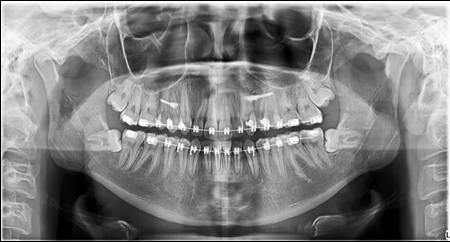

The panoramic radiograph showed bilateral mandibular third molars. The level of alveolar bone crest was within the normal range. (Figure 3)

Figure 3.Pretreatment panoramic X-ray

Before the finishing stage, a panoramic x-ray was taken. The third molars were removed .(Figure 6)

Figure 6.Panoramic X-ray before the removal of the third molars.